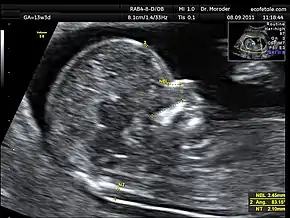

![]() Measurements of fetal nuchal translucency, nasal bone and facial angle according to the standards of the Fetal Medicine Foundation | |

Procedure

Nuchal scan (NT procedure) is performed between 11 and 14 weeks of gestation, because the accuracy is best in this period. The scan is obtained with the fetus in sagittal section and a neutral position of the fetal head (neither hyperflexed nor extended, either of which can influence the nuchal translucency thickness). The fetal image is enlarged to fill 75% of the screen, and the maximum thickness is measured, from leading edge to leading edge. It is important to distinguish the nuchal lucency from the underlying amniotic membrane.[8]

Normal thickness depends on the crown-rump length (CRL) of the fetus. Among those fetuses whose nuchal translucency exceeds the normal values, there is a relatively high risk of significant abnormality.